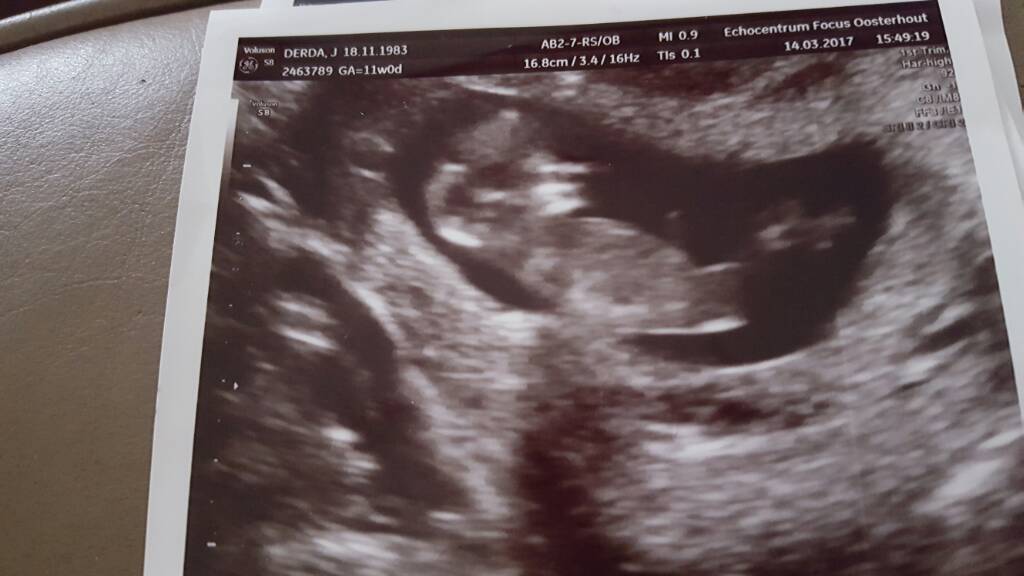

Jestem. Dzięki kochane za kciuki. Wszytko ok. Serduszko jak dzwon. Krasnoludek ma już prawie 5 cm (4.84):-). Według om dzisiaj 11t0d według usg 11t3d także rośnie jak na drożdżach. No i po usg mam termin ustalony na 29.09 :-)

1489509638-aaaaaa.jpeg